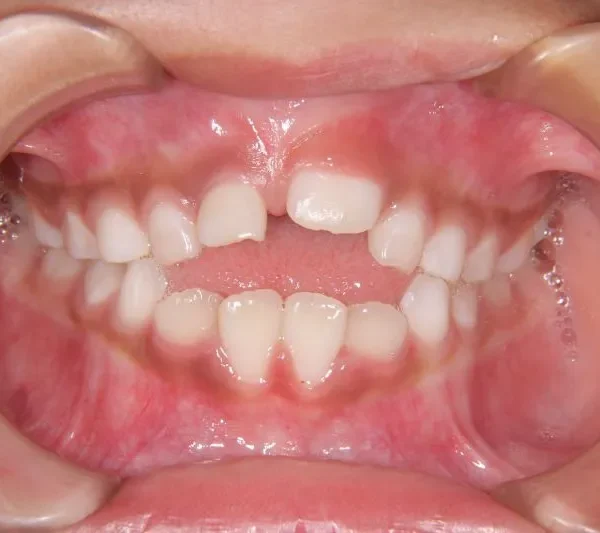

状態 前歯で噛めない(開咬/オープンバイト)

1.主訴 前歯がかみ合わない・出っ歯

2.診断名あるいは主な症状 開咬

前歯がかみ合っていません。

前歯は物を噛みちぎる(ハサミのような)役割をするのですが、歯と歯が離れていて本来の役割を果たしていません。

硬いものが嫌いな方や、噛むことが苦手な方に見受けられます。このまま、噛まずにいると

将来歯が残りにくくなります。